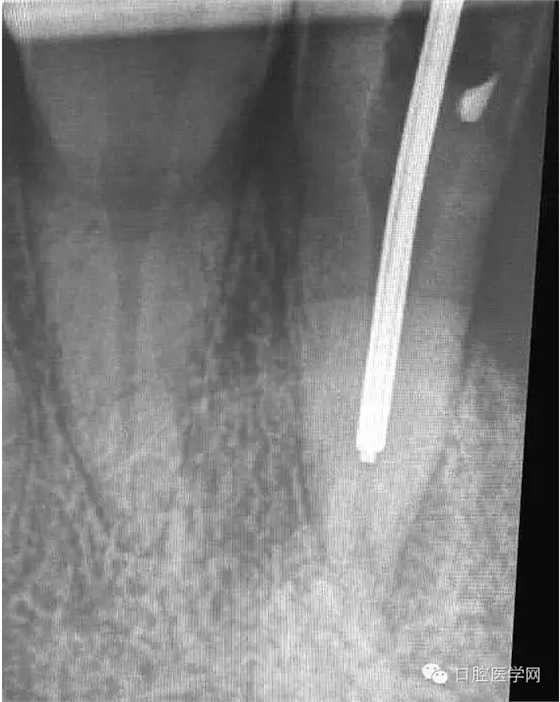

1.先根測(cè)根長(zhǎng),再用機(jī)擴(kuò)對(duì)根管進(jìn)行預(yù)備;

2.用2%次氯酸鈉+2%氯己定+17%EDTA交替沖洗,在用超聲蕩洗。干燥,封氫氧化鈣十天。

3.十天之后復(fù)診,無明顯癥狀,。準(zhǔn)備再次用2.5%次氯酸鈉+2%氯己定+17%EDTA交替沖洗,在用超聲蕩洗。